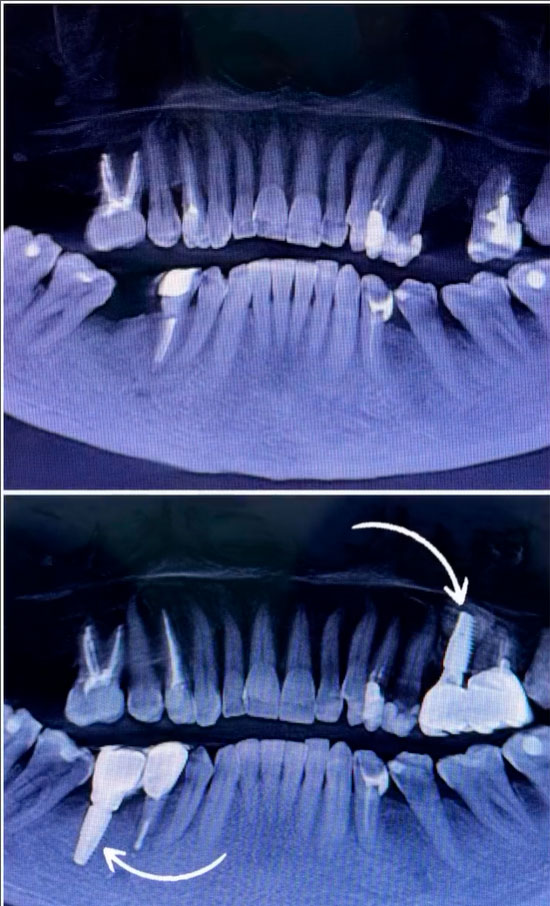

Большая операция по установке имплантатов. Все прошло отлично!

Видео здесь >>>Врач-стоматолог-хирург-имплантолог Сарасеко ОксанаТел.: +375 29 814-11-88.